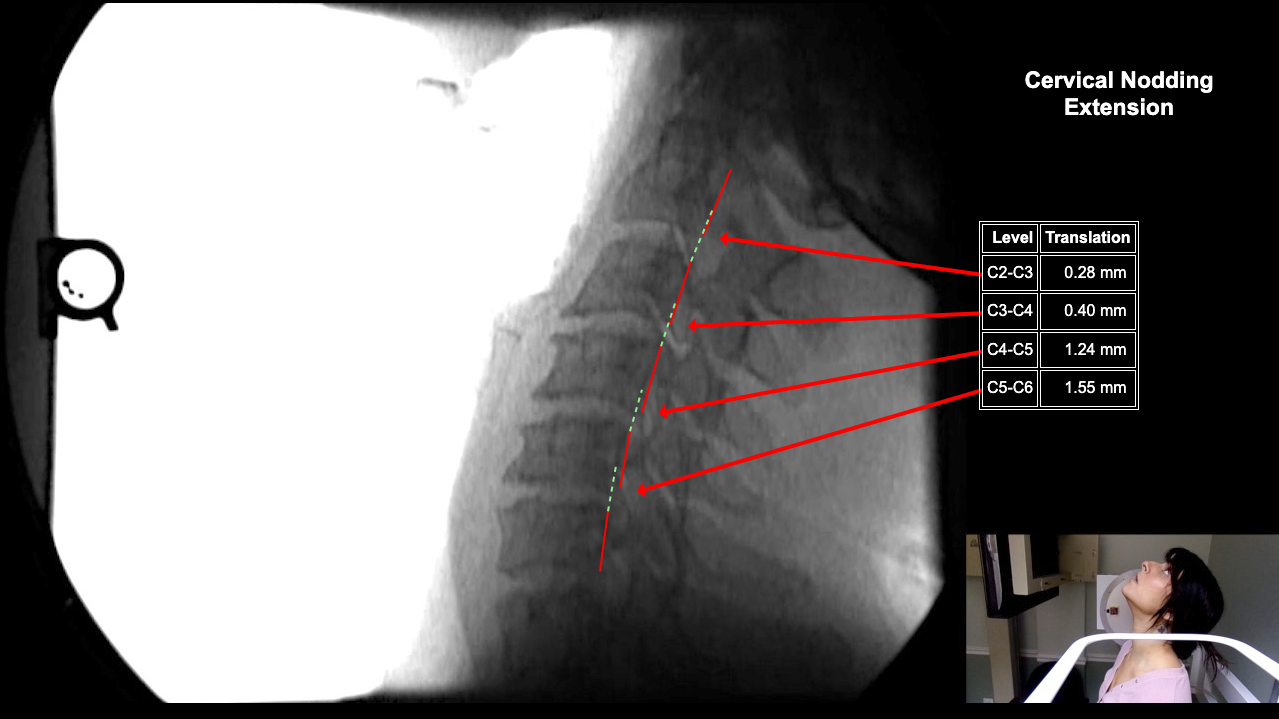

Image 2